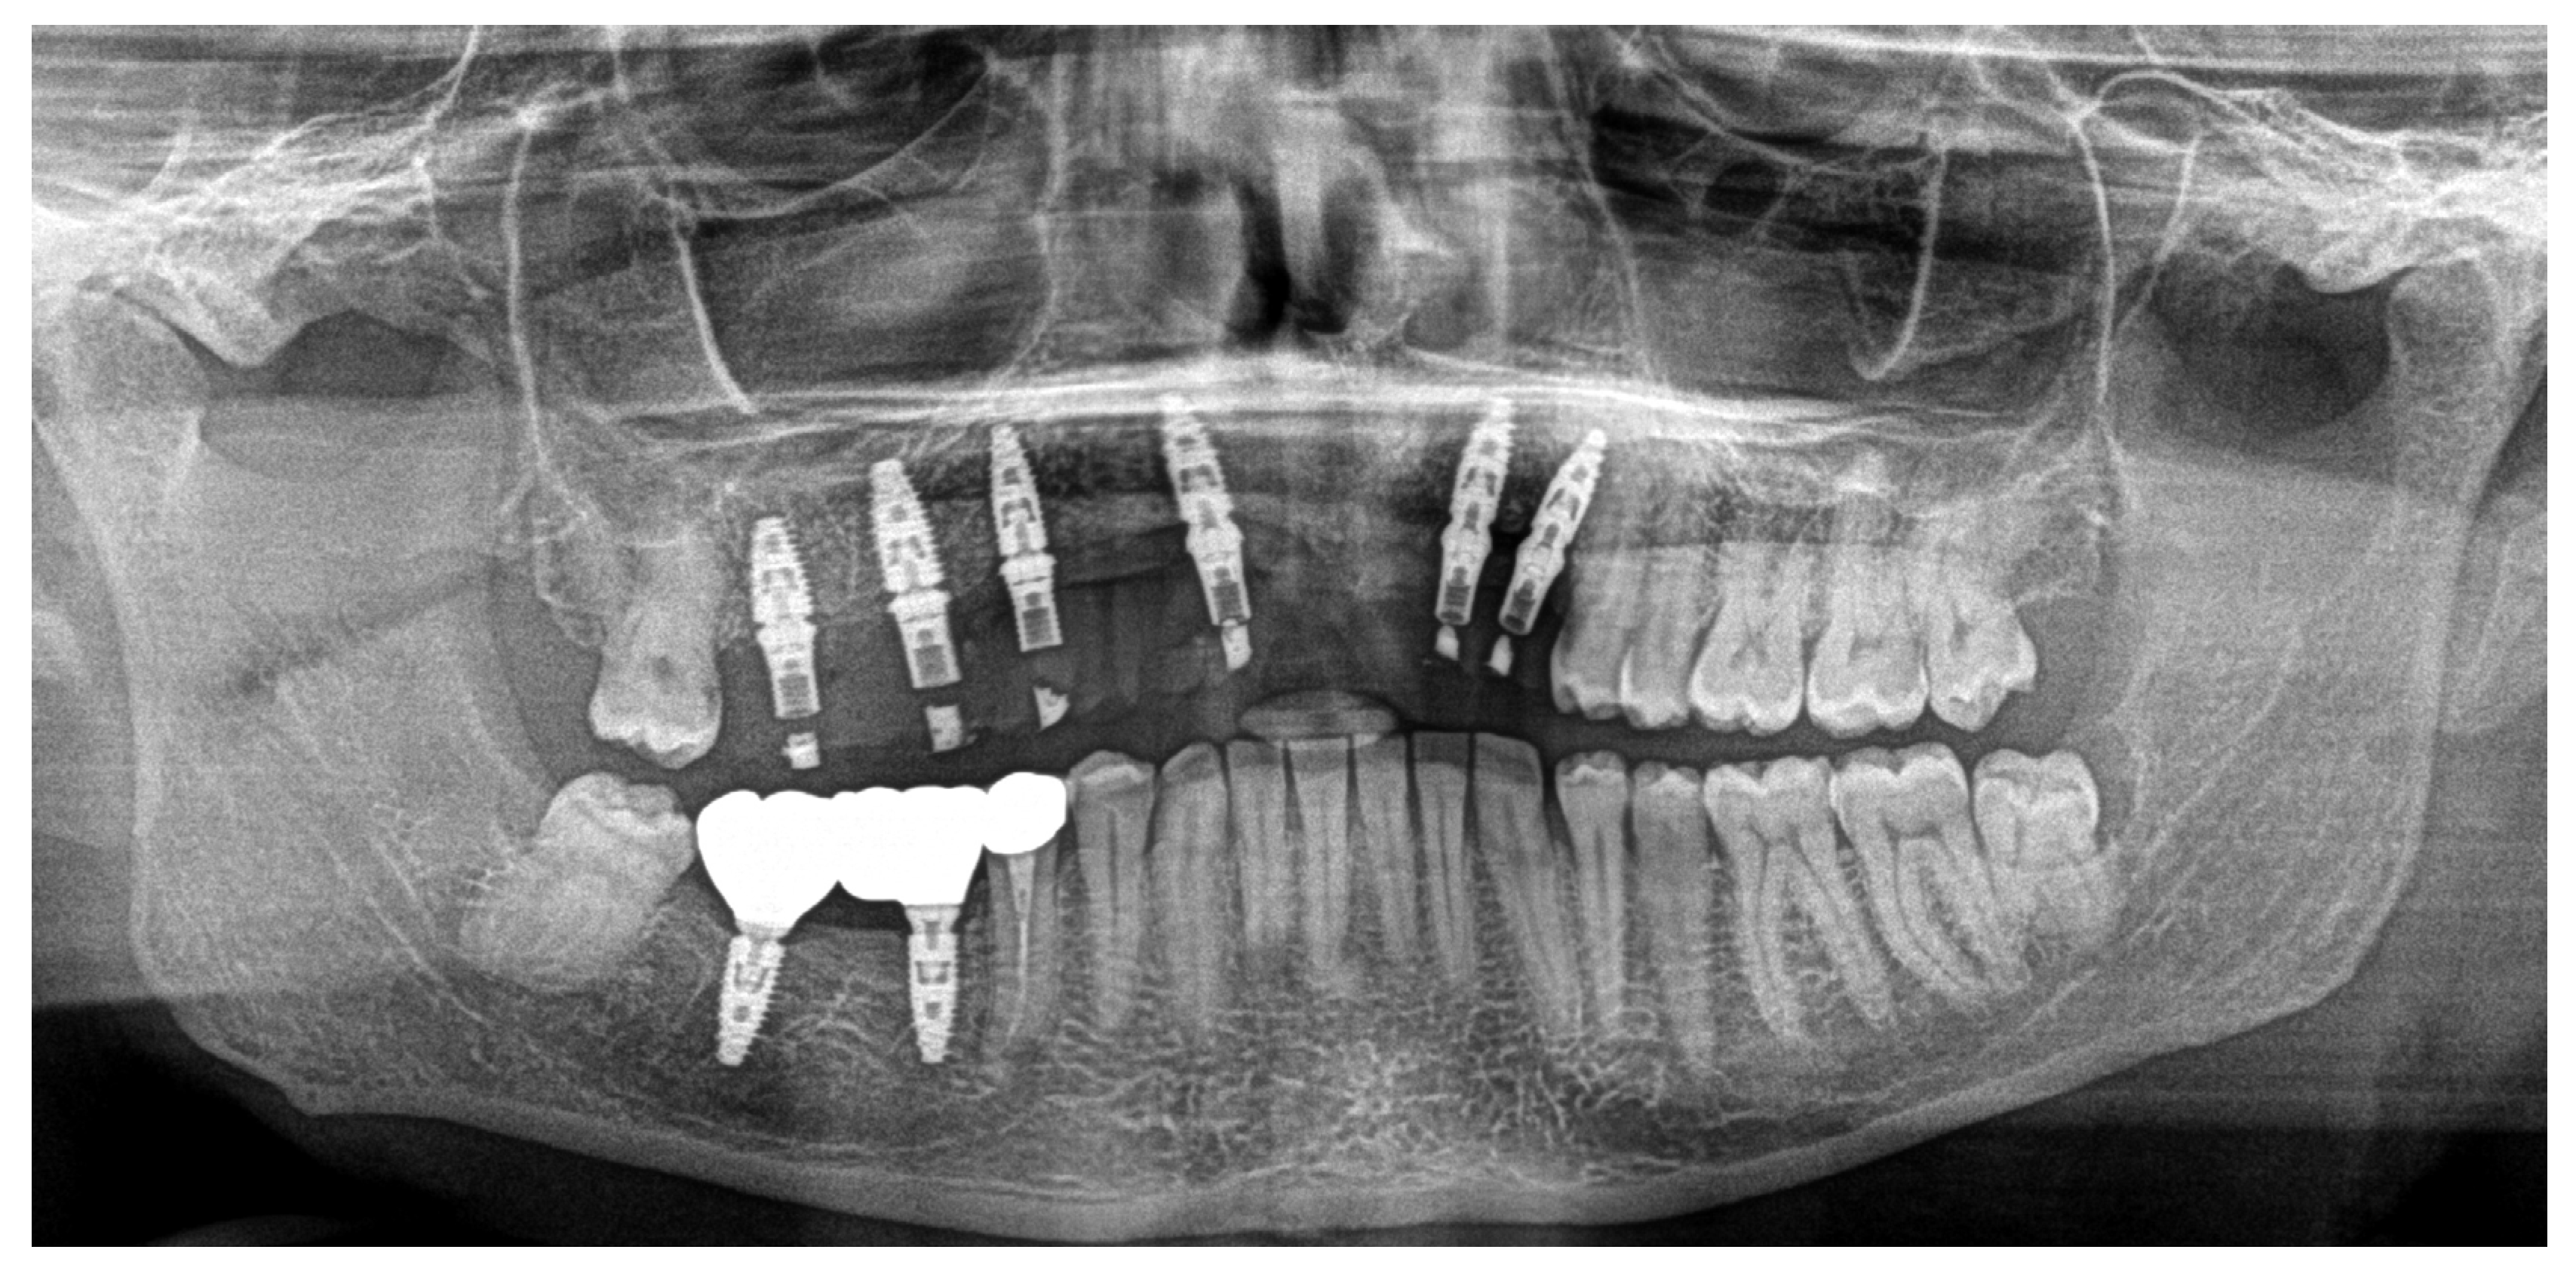

Based on previous experience and the speed of their development, in January 2023, it was decided to extract teeth 14 and 15, 46 and 47, decontaminating the alveoli, regenerating with PRF (in order to promote healing of the defect) and heterologous bone. So, the site was treated with a mix of Bio-Oss granules 25 (Geistilich Bio-Oss-Geistlich Pharma AG, Wolhusen, Switzerland), autologous bone chips, platelet-rich fibrin (PRF), and collagen membranes (45% Bio-Oss 25, 45% PRF, 10% autologous bone chips). Simultaneously, four implants (3.6 × 10 mm, Biotech Dental, Allée de Craponne, Salon de Provence, France) were inserted in the upper edentulous area, completely submerging them. However, an initial rejection of three of the four implants was observed (about 20 days after insertion), which made it necessary to remove them, decontaminate them with dye-free photodynamic therapy, and reinsert them 120 days later, when the implants were also inserted in areas 46-47 (3.6 × 10 mm and 4.2 × 10 mm, Biotech Dental, Allée de Craponne, Salon de Provence, France) in June 2023 (Figure 7).

Figure 7. Ortopantomography (OPT) post-surgery in September 2023.